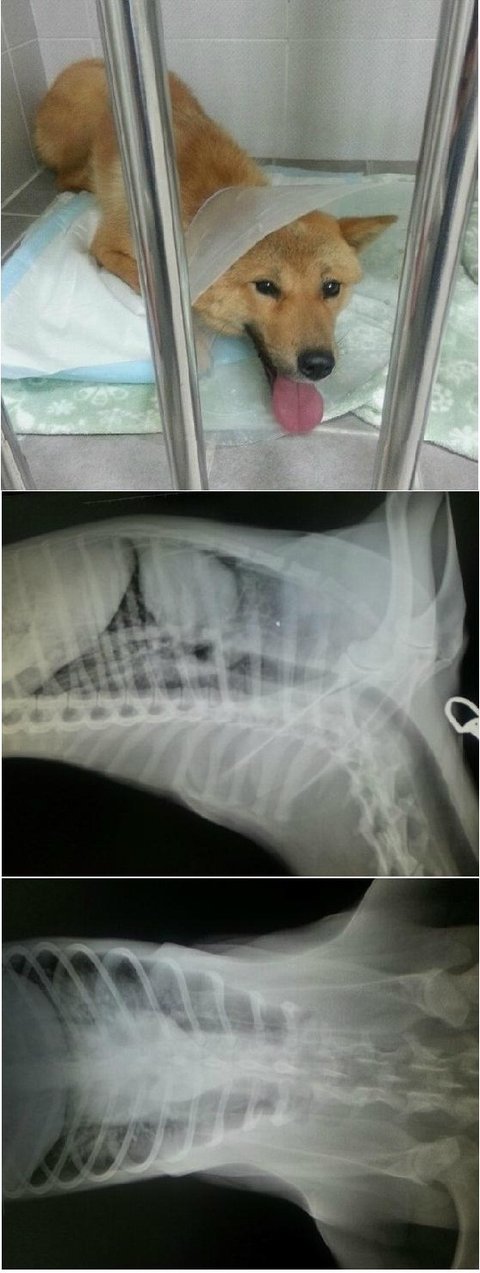

응급실에 있는 백구

백구라고 알고 갔는데 나이 어린 황구였어요.

한 두살 먹은 남아구요. 너무 너무 순한 아이입니다.

현재 폐출혈이 있고 오른쪽 뒷다리가 골절된 상태에요.

폐의 출혈이 멈춰진다면 별 문제없이 다리 수술에 들어갈 수 있지만

사고 시각을 정확히 알 수 없기 때문에 내일 오전중에 다시 검사를 해야 한다고 합니다.

만약 폐출혈이 더 악화된다면 정말 위험하구요.

피검사 결과 백혈구 간수치 외엔 정상이였구요. 심장 사상충도 음성반응 나왔습니다.